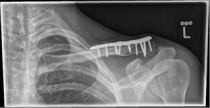

Picture 1                                                                Picture 2

Picture 1: Displaced fracture of the left collarbone before surgery.